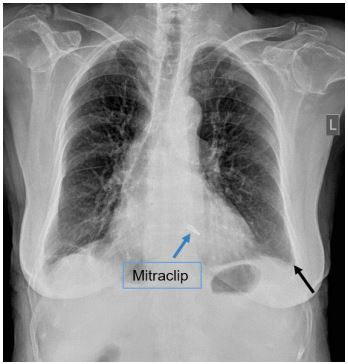

Bedside echocardiography was performed and showed mild circumferential pericardial effusion, without evidence of hemodynamic compromise (Figure 2). A chest X-ray revealed a small left pleural effusion (Figure 3). Echocardiographic studies from day 1 and 2 after the initial operation were reviewed and did not show any pericardial effusion. Thus, the patient had a newly developed pericardial effusion on day 3. Laboratory exams showed elevated white blood cells and c-reactive protein, with negative values of procalcitonin and negative blood cultures on multiple samples. Mechanical and infectious causes of pericardial effusion had been excluded. Post-cardiac injury syndrome was considered as a possible working diagnosis.

Figure 3: Chest X-ray revealed a small left pleural effusion (black arrow).